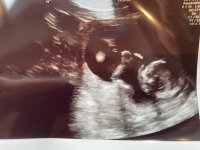

12+5 (målt til 13+0) i går, alt bare vel der inne :love017 Jordmor var veldig sikker på at den lille krabaten er ei jente:Heartred